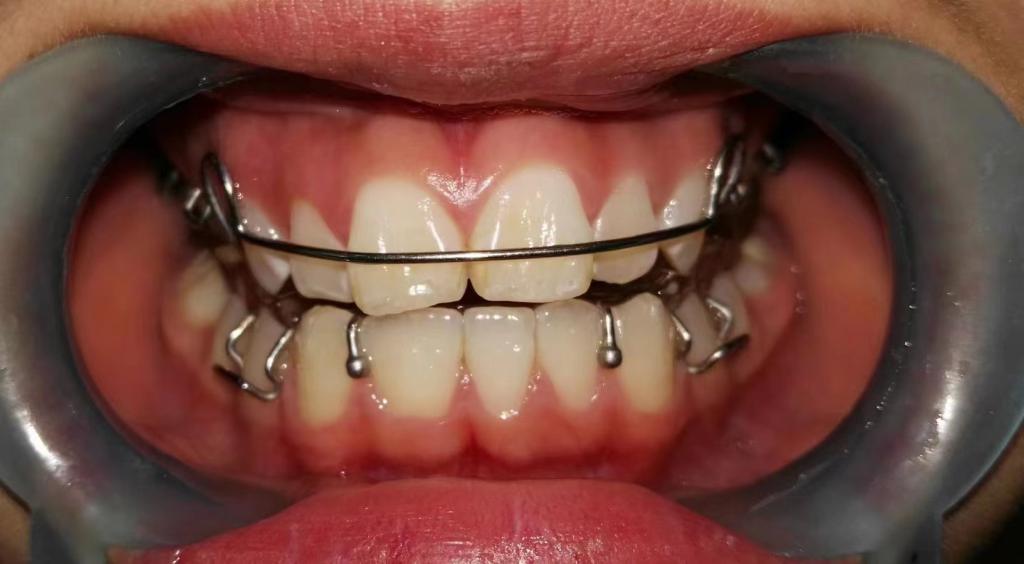

3. 前牙深覆合深覆盖

前牙深覆合是指上前牙覆盖下前牙唇面超过1/3,深覆盖是指上前牙的唇面与下前牙唇面之间的水平距离超过3mm,常常伴有下颌后缩,侧貌呈现凸面型。

矫治方法:前牙深覆合深覆盖的患儿常常伴有吮指,咬下唇,口呼吸等不良习惯,同样,应首先纠正其不良习惯,必要时可在其手指上涂抹苦瓜汁或是辅助矫治装置如唇挡丝、前庭盾等。同时早期可进行肌功能训练,如上唇肌张力训练。口呼吸习惯应进行耳鼻喉科会诊处理,检查其是否伴有鼻咽部疾病,排除鼻咽部疾病后,再使用前庭盾、闭口贴等纠正。针对功能性的因素,常用的矫治器为肌激动器,TB、FRⅡ。针对骨性的因素,常用的矫治器为头帽-肌激动器。